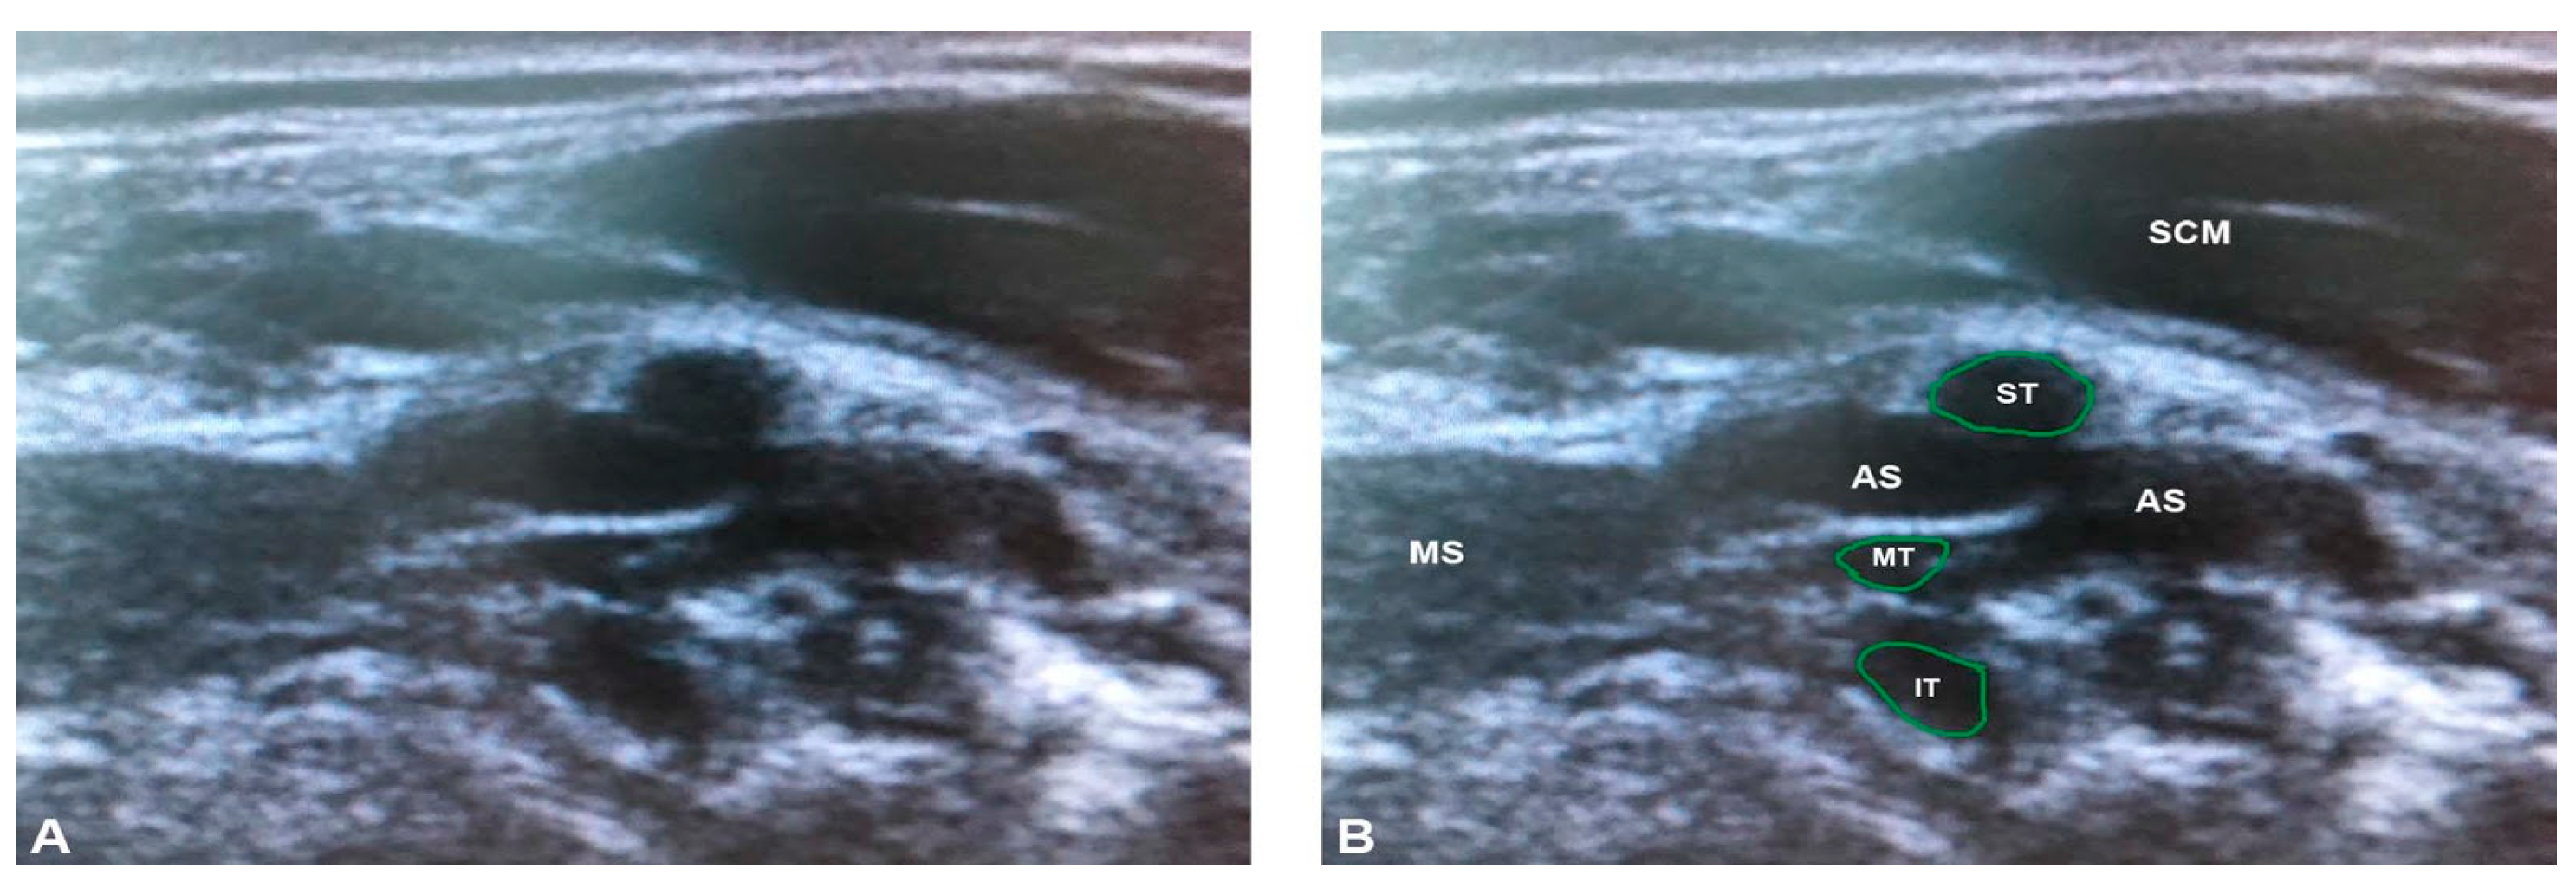

3.2. Ultrasonographic Results